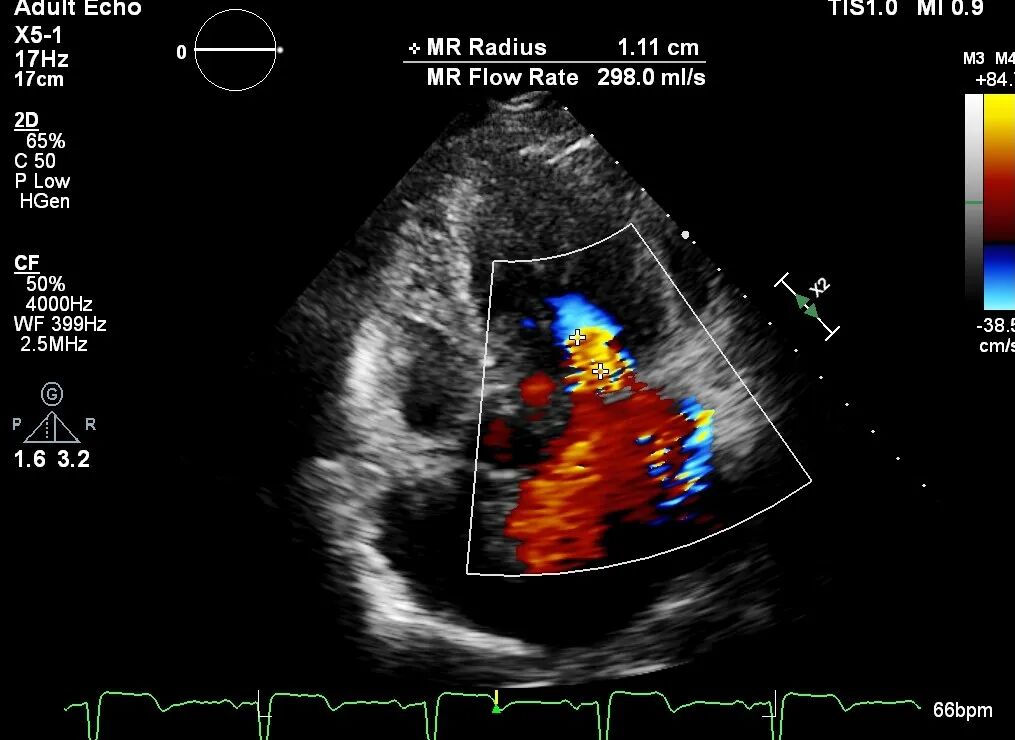

二尖瓣重度反流,EROA=0.59 cm²;RV=106ml;三尖瓣少-中等量反流,PASP: 42 mmHg;左心增大,左室收缩功能减弱。

原发性MR,交界C1区脱垂,反流程度4+;二尖瓣瓣口面积3.88cm²,平均跨瓣压差2mmHg;二尖瓣前叶(A1)长度16.2mm,二尖瓣后叶长度(P1)长度9.9mm,脱垂高度6mm。

反复测试二尖瓣夹的稳定性,食道超声复查提示二尖瓣夹C1区反流有效改善,术后反流量由术前的4+变为术后的<1,遂精准释放二尖瓣夹。